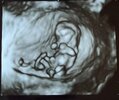

Ja po wizycie, wszystko dobrze, bobas ma już 3,3 cm długości 🤩 Dwie ręce, dwie nogi, wszystko się zgadza, ruchliwy mocno😃 Słyszałam serduszko ❤️ Dostałam skierowanie na ponowne zbadanie TSH, bo mam na granicy normy. Poza tym wszystko luks. Jestem mega zadowolona z nowej lekarki, bo USG robiła baaardzo dokładnie, wszystko mi pokazywała, tłumaczyła. Mam nawet piękne fotki 3D 🤣

• IMG_2093.jpeg

IMG_2093.jpeg

618,5 KB · Wyświetleń: 41